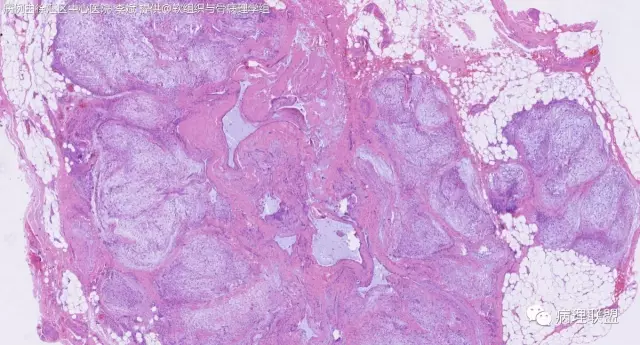

女,64岁,右腕部肿块,灰白不整形1*1*0.8cm(病例由徐汇区中心医院 李斌提供,致谢!)

神经鞘粘液瘤。

富于细胞神经鞘粘液瘤,s100阴。

关节旁粘液瘤,肿瘤中间明显有腱鞘囊肿结构,又发生在关节处!强烈提示为关节旁粘液瘤,部分病例可以呈分叶结构!平时多加观察腱鞘囊肿囊壁常可见粘液变性!范围一广就成粘液瘤样。